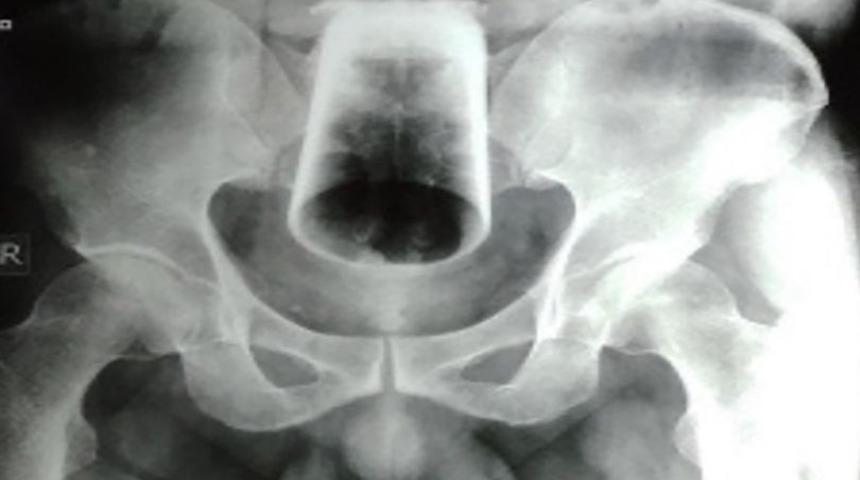

Nepal’de yaşayan 47 yaşındaki ismi açıklanmayan bir adam doktorları şaşkına çeviren bir duruma imza attı. Büyük bir acı ve tuvaletini yapamama şikayetiyle hastaneye başvuran adamın yapılan tetkiklerde kalça bölümünde cam bir su bardağı olduğu tespit edildi. 3 gün boyunca cam bardakla birlikte yaşayan adam acil bir şekilde ameliyata alındı.

İki gün boyunca tuvaleti kullanamadığı için büyük bir acı çeken adam sarhoşken cam bardağı anüsünden içeri soktuğunu günler sonra hatırlamayı başardı. İtirafının sonrasında ismi açıklanmayan adamın tıbbi durumu Journal Of Nepal Medical Association dergisindeki yerini aldı.